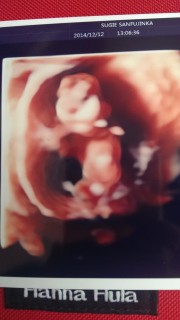

赤ちゃん元気にしてますよと先生に言われて一安心!お産もできる病院に変えたので不安がありましたが4Dでもエコー確認出来ました!次の検診は4週間後(´・_・`)待ち遠しいです!

CRL49,7㎜

大きさは49.1mm。